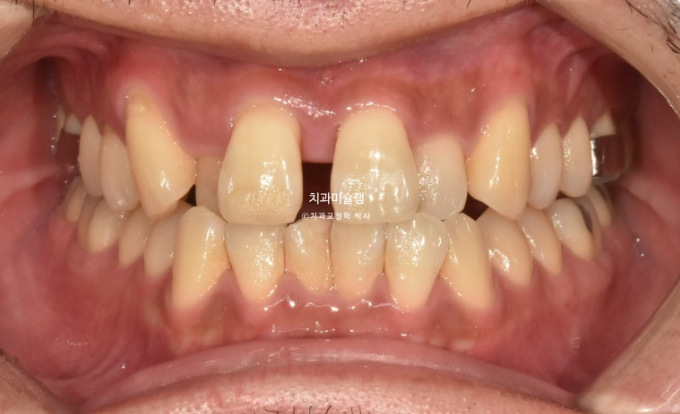

덧니가 있고 위아래 치아 중심선이 어긋나 있습니다.

치아중심선이 어긋나 있는 것은 아래턱 비대칭이 있기 때문입니다.

그에 비해 뒤쪽 어금니 교합은 좋은 편 입니다.